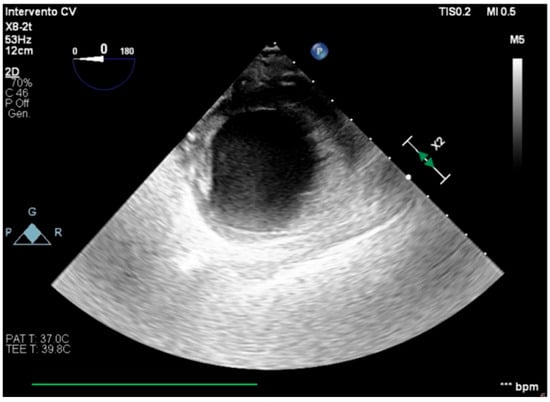

We describe a case of a 75-year-old woman affected by a post-myocardial-infarction ventricular septal defect (VSD) and a left-ventricle (LV) apical aneurysm. The patient underwent surgery for VSD closure and aneurysm exclusion. The patient had a STEMI (ST-elevation myocardial infarction), with evidence of occlusion of the anterior interventricular artery, for which thrombus aspiration and stenting of the left coronary artery and proximal anterior interventricular artery was performed. Then, she developed cardiogenic shock with pulmonary edema and thus required the support of an IABP (intra-aortic balloon pump) of C-PAP and levosimendan in continuous infusion for 24 h. Seven days after the event, a large post-infarct VSD at the apical level with a left–right shunt occurred. She was therefore transported from the spoke center to our hospital and underwent surgical treatment, namely, post-infarct VSD closure and exclusion of a left ventricular aneurysm. The intra-operative transesophageal echocardiography showed concentric LV remodeling, slight dilatation, LVEF 28% (Figure 1), and akinesia of the mid-apical segments in toto with aneurysmal evolution (Figure 2).

Figure 1. Mid-esophageal four-chamber view.